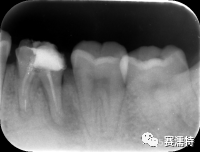

祝自洋老師案例

張云鳳老師案例

張凈玉老師案例

喻剛老師案例

楊艷老師案例

楊超老師案例